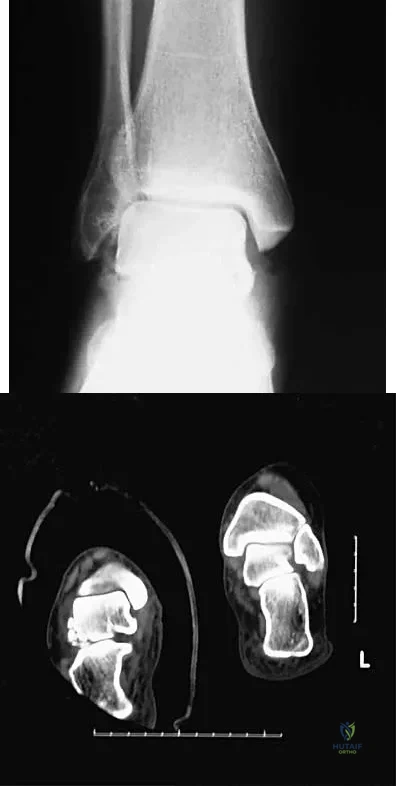

An 11-year-old boy has had a fever and pain and swelling over the lateral aspect of his right ankle for the past 3 days. Examination reveals warmth, swelling, and tenderness over the lateral malleolus, and he has a temperature of 103.2 degrees F (39.5 degrees C). Laboratory studies show a WBC count of 13,200/mm3 with 61% neutrophils, an erythocyte sedimentation rate of 112 mm/h, and a C-reactive protein of 15.7. Radiographs and a T2-weighted MRI scan are shown in Figures 13a through 13c. Aspiration yields 1 mL of purulent fluid. Management should now consist of

Explanation